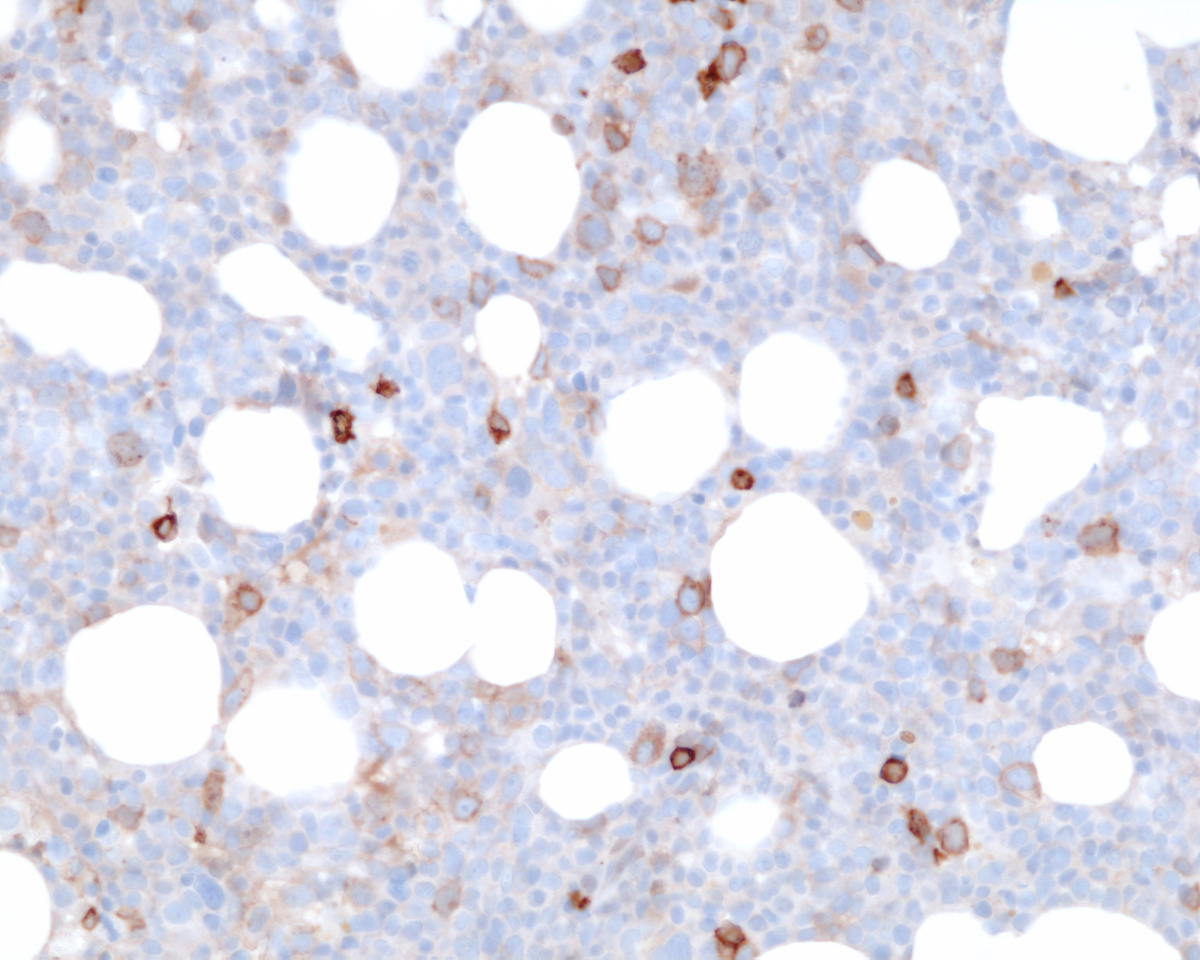

Immunohistochemical stains showed marked increase of megakaryocytes, including numerous small, monolobated forms, which are strongly positive for CD61. CD34 and CD117 highlight increased immature cells, approximately 10% of the nucleated marrow elements. Reticulin shows mild diffuse increase in fiber deposition. An iron stain shows adequate stainable iron. Immunophenotyping by flow cytometry reveals approximately 7% of the total gated events in the dim CD45 positive gate, which coexpress CD34, CD117 and myeloid antigens. A subset of the cells coexpress CD41 and CD61 indicating megakaryocytic lineage.

| Immunohistochemistry CD61 | ![]() |